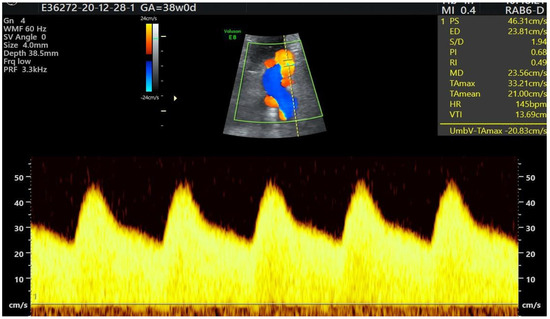

- PS UV;

| Color Doppler |